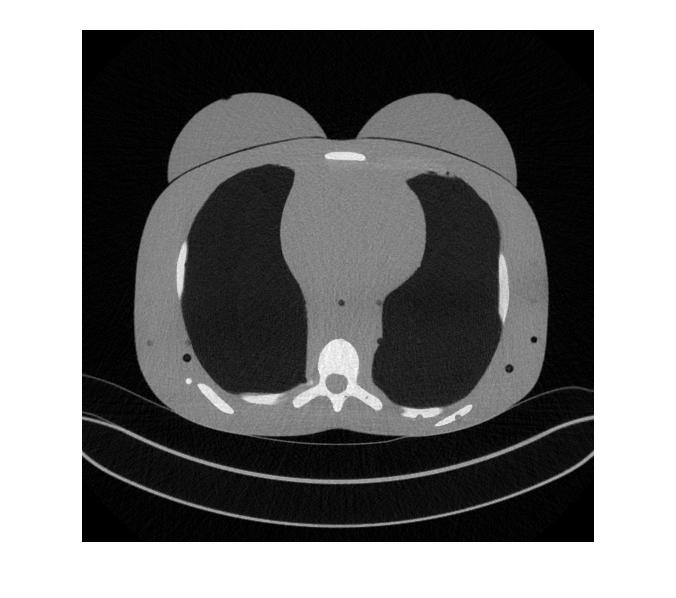

II-C CT Image Visualization

We begin by visually comparing the ROI selected by the WFDM method to that of the baseline method. Fig. 3 demonstrates the baseline thresholding method from Fig. 1 now applied to an image taken from a patient at 48m​Aπ‘šπ΄mA tube current. Fig. 3(a) is the original image scaled to [0,1]01[0,1] and Fig. 3(b) is the mask acquired by thresholding pixel intensities such that [0.4,0.7]=10.40.71[0.4,0.7]=1 and the remaining pixels are set to 00. The ROI shown in Fig. 3(c) results from further narrowing the threshold so that [0.5,0.6]=10.50.61[0.5,0.6]=1 and the remaining pixels are set to 00. In addition, these threshold ranges were chosen empirically, hence the baseline method is not generalizable.

Conversely, applying WFDM to the same CT image shown in Fig. 3(a) and thresholding at [q<IDΒ―4]delimited-[]π‘žΒ―subscriptID4[q<\frac{\overline{\rm I_{D}}}{4}], where IDΒ―Β―subscriptID\overline{\rm I_{D}} is the mean distance in IDsubscript𝐼𝐷I_{D}, results in the mask and corresponding ROI-LV shown in Fig. 4, respectively. Here, we observe the qualitative variations between the original image and the masked ROI-LV image. First, edges, as well as regions of high spatial variation such as the spine, have been removed. Second, the selected regions are not necessarily of the same absolute pixel intensity, as compared with the ROIs shown in Fig.3. Finally, the masked ROI-LV region in Fig. 4(b) is selected by relative thresholding as opposed to fixed intensity thresholding in the baseline method. Thus, the proposed WFDM based ROI-LV masking method is generalizable.

Refer to caption

Figure 3: A CT image from the patient data imaged at 48m​Aπ‘šπ΄mA tube current. (a) The original CT image, (b) a mask of ROI acquired by fixed thresholding [0.5,0.6]=10.50.61[0.5,0.6]=1, and (c) a mask of ROI acquired by fixed thresholding [0.525,0.575]=10.5250.5751[0.525,0.575]=1.

Figure 4: The same CT image as in Fig. 3(a) after processing with WFDM. (a) A mask ROI-LV and (b) the masked ROI-LV are observed.